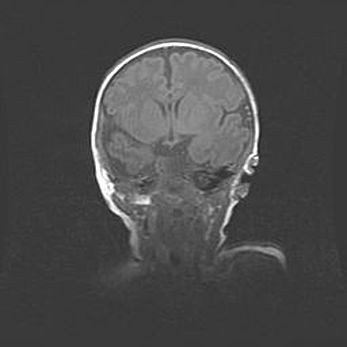

Сообщающаяся гидроцефалия. Кистозная энцефаломаляция головного мозга.

Возраст: 3 месяца 4 дня

Вес: 3100 г

Пол: женский

Окружность головы: 34 см

Срок гестации: 31 неделя

Кистозная энцефаломаляция головного мозга - одна из форм поражения головного мозга в детском возрасте. Характеризуется возникновением множественных и распространённых кист в коре, белом веществе и подкорковых образованиях головного мозга у плодов, новорождённых и детей раннего возраста. Развитие кистозной энцефаломаляции связано с внутриутробной асфиксией и гипотонией, родовой травмой, тромбозом синусов, пороками развития сосудов, инфекциями, сепсисом и другими причинами. Наиболее значимые инфекционные агенты: вирусы простого герпеса, цитомегалии, краснухи, токсоплазмы, энтеробактерии, золотистый стафилококк и другие.